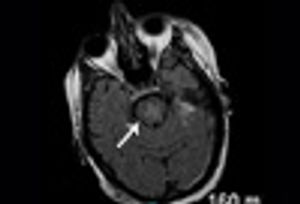

Lhermitte-Duclos disease is a rare, slow-growing, benign lesion of the cerebellum and is considered a hamartomatous tumor of the cerebellar cortex.